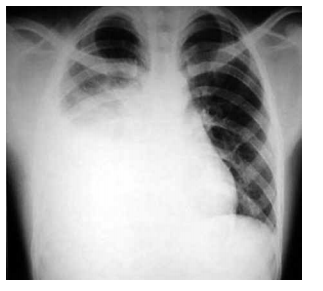

Leia o enunciado a seguir e responda a questão.

Paciente do sexo feminino, 66 anos, com antecedentes de tabagismo, hipertensão arterial sistêmica e diabetes mellitus tipo 2, procura atendimento médico com queixa de desconforto retroesternal tipo queimação e opressão que se iniciou há 1 mês, desencadeado aos grandes esforços. Há 1 semana passou a apresentar os mesmos sintomas em repouso, associados à dispneia, com duração de até 8 minutos e melhora espontânea. A paciente faz uso de valsartana 80 mg, glimepirida 4 mg e metformina 1000 mg. O exame físico é normal, PA = 150x85 mmHg e frequência cardíaca de 96 bpm. O eletrocardiograma está ilustrado a seguir.